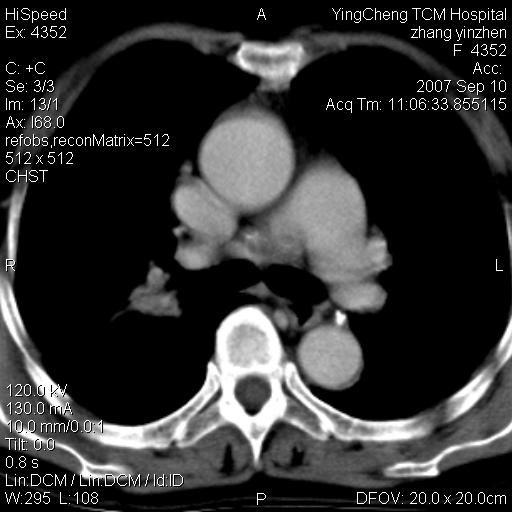

以下是引用卜一在2007-9-18 14:41:00的发言:[br]右肺肿块:毛刺+胸膜凹陷征+供血血管+浅分叶+强化。支持:周围性肺癌 !另:左侧甲状腺腺瘤!

以下是引用夏季在2007-9-18 11:00:00的发言:[br]1。右肺肿块,周围有短毛刺,肺门侧有血管与其相连,胸壁侧有胸膜凹陷征,考虑周围性肺癌 2。左侧甲状腺软组织肿块,内有高密度钙化灶,考虑左侧甲状腺腺瘤。